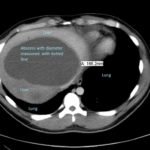

Although rare in the developed world, amebic infections are common worldwide and represent a challenging and often overlooked diagnosis. In this case, an amebic liver abscess was discovered in a 29-year-old male who presented to the emergency department (ED) complaining of right upper quadrant abdominal pain, weight loss, non-bilious/non-bloody vomiting, and diarrhea for three months. He recently traveled to India and Mexico. Point-of-care ultrasound discovered a liver mass and computed tomography (CT) confirmed the presence of a liver abscess. The case highlights the usefulness of ultrasound as an initial diagnostic tool, the importance of careful travel history in patients with suspected infectious diseases, and the initial provision of broad-spectrum coverage for bacterial and amebic pathogens for liver abscesses until the pathogen has been identified.